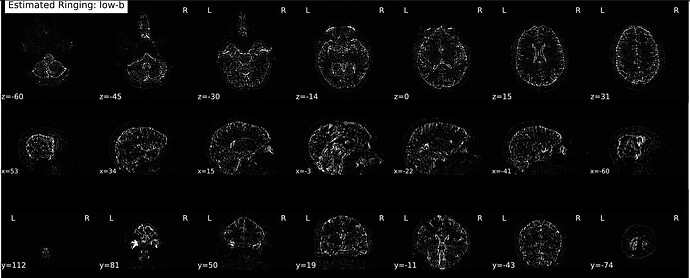

So I thought maybe it might have something to do with running dwidenoise first—went and tested out RPG on a couple raw scans (no reorenting to LPS or MP-PCA, just run locally on my machine via the TORTOISE Docker container), and much to my surprise…

It switched! Now the cutoff is a bit more rostral along the PE axis and it’s just the posterior portion of the brain that seems to have estimated/removed Gibbs artifacts. Here’s an example from a cs-DSI collected in May of this year (absolute value overlaid after subtracting the first raw and unrung b=0 volume):

And one using the Q4 sampling scheme (same site but prior to a gradient coil replacement):